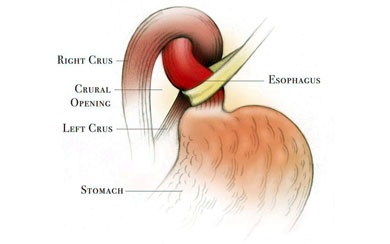

- Disponibilitate hernie hiatala (HH) dislocă sfincterul esofagian inferior a mari zone intraabdominale în zona de joasă presiune intratoracică, care poate provoca reflux gastro-esofagian.

Tratamentul chirurgical al bolii de reflux gastroesofagian într-un volum fundoplication laparoscopica necesita un anumit procent de pacienti cu GERD. Obiectivele operațiunii sunt de a „strânge“ zona de joncțiune-esofagian gastric, de a genera supapă suplimentară a fundului de ochi al stomacului și, dacă este posibil, reducerea herniei hiatale a stomacului, care este frecventa la copii cu reflux gastroesofagian.

Scopul interventiei chirurgicale este de a restabili bariera antireflux, fără a crea obstacole în calea bolului. Nissen fundoplicatură - chirurgie antireflux, în care folie gastric în jurul părții inferioare a esofagului 360 °. creând o manșetă care previne conținutul gastric în esofag. Inainte de operatie, pacientii ar trebui sa fie examinate cu atenție, o atenție deosebită trebuie acordată la ultimul etaj al radiografiei tractului gastro-intestinal pentru a exclude alte posibile boli.

- mobilizarea fundus gastrice și cardia;

- excizia sacul herniei și suturarea diafragmei la picioarele HH.